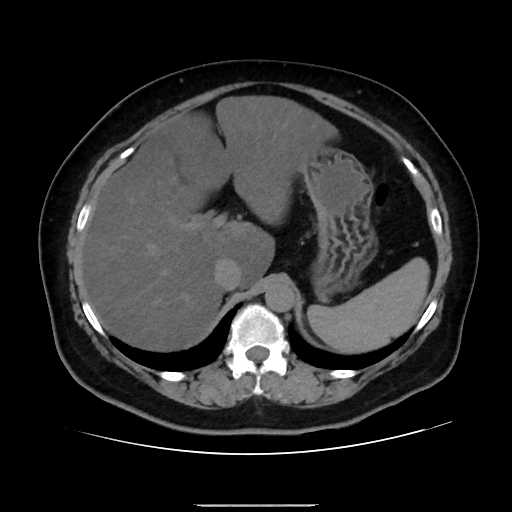

腹部

脂肪肝